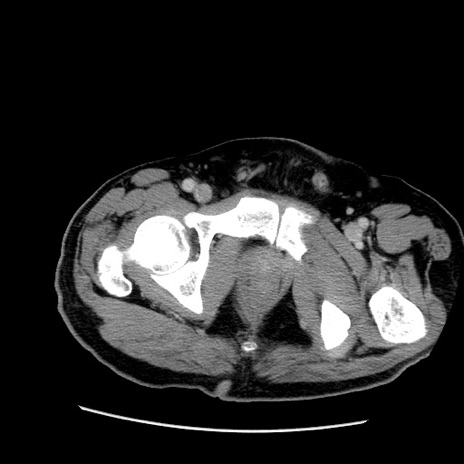

冠状断像

【症例】50歳代男性

【主訴】腹痛

【現病歴】AVMからの被殻出血のため回復期リハ病棟入院中。 本日午後3時頃急に下腹部痛が出現した。

【既往歴】AVM、被殻出血、虫垂炎、高血圧

【身体所見】意識晴明、左半身不全麻痺、会話の理解は良好、36.5°C、腹部:膨隆、全体に板状硬、下腹部正中に圧痛点あり、反跳痛-、筋性防御不明、右下腹部にope scar

【データ】WBC 9400、CRP 0.06